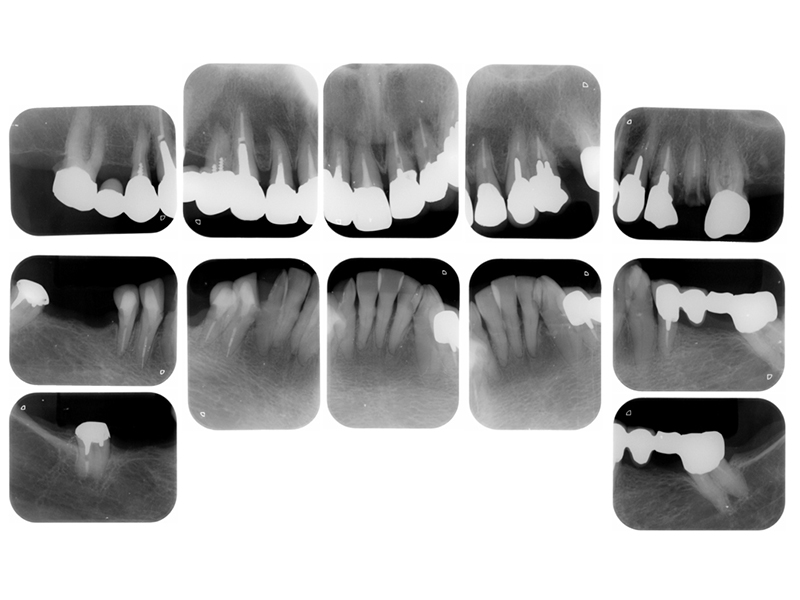

初診時X線写真

治療終了時